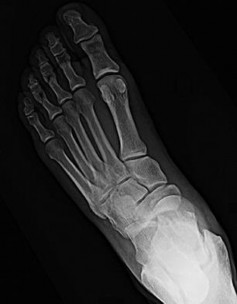

A 42-year-old man with diabetes presents for treatment of a swollen foot (Slide). He does not recall the onset of swelling, and he states that his foot is not painful. On examination, the foot is hot to touch and swollen. Upon radiographic examination, no deformities are evident. Which of the following treatment options should be used next: